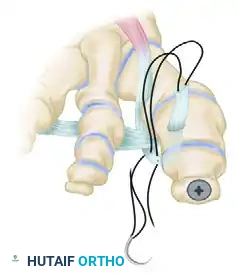

Step 5: EHL Tendon Routing and Transfer

With the IP joint securely fused, attention is turned to the dynamic correction of the MTP joint. The goal is to route the EHL tendon to act as a lateral collateral ligament substitute and a plantarflexor.

- Identify the deep transverse metatarsal ligament in the first web space.

- Pass the mobilized EHL tendon plantar to the deep transverse metatarsal ligament. This critical step changes the vector of the EHL pull from dorsal-medial to plantar-lateral.

- Route the tendon dorsally to the base of the proximal phalanx.

- Prepare a drill hole through the base of the proximal phalanx from lateral to medial. Pass the EHL tendon through this osseous tunnel.

- Apply tension to the EHL tendon while holding the MTP joint in approximately 10 to 15 degrees of extension and neutral coronal alignment (correcting the varus).

- Suture the tendon back onto itself using non-absorbable braided suture (e.g., #2-0 FiberWire or Ethibond) to secure the transfer under appropriate physiological tension.

Clinical Pearl: The tensioning of the EHL transfer is the most technically demanding aspect of the procedure. Over-tensioning will result in a rigid, plantarflexed MTP joint that causes significant pain during the toe-off phase of gait. Under-tensioning will fail to correct the varus deformity. The toe should rest naturally in neutral alignment without manual support once the tendon is secured.